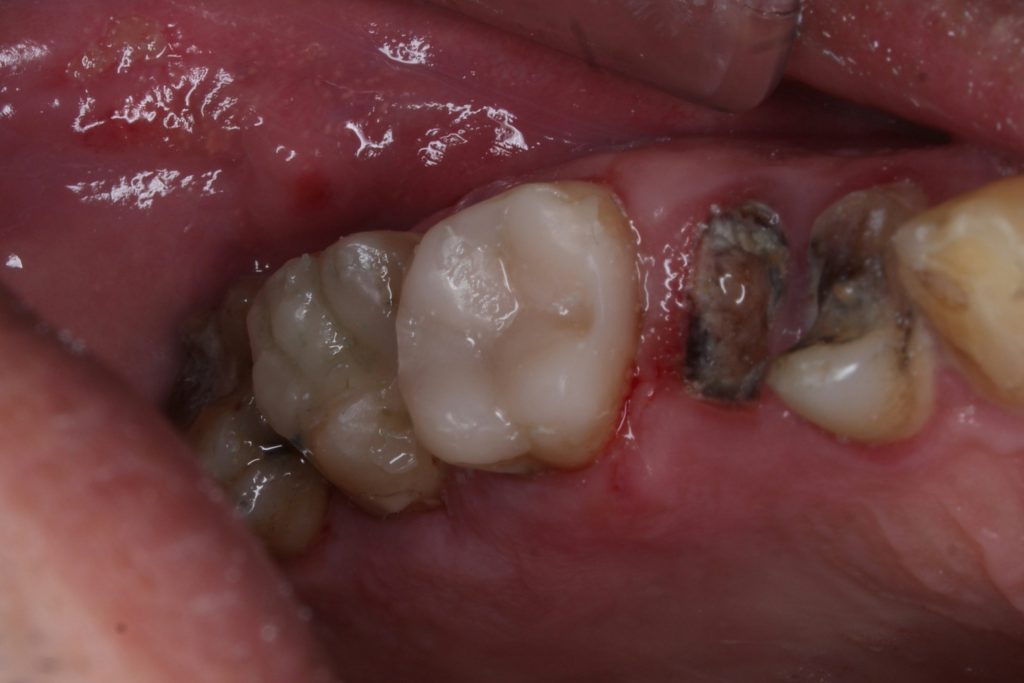

A matrix system was properly adapted to ensure proximal contact and contour. The cavity was etched, bonded, and restored incrementally using nanohybrid composite resin. Each layer was light-cured thoroughly.

After finishing and polishing, the occlusion was checked and adjusted to eliminate any premature contacts. The final restoration achieved excellent marginal adaptation, anatomical contour, and aesthetic appearance.